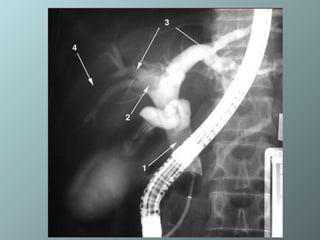

Colangiopancreatografía Retrógrada Endoscópica (CPRE) Es un procedimiento endoscópico utilizado para evaluar el sistema ductal pancreático y biliar y está indicado en la pancreatitis aguda  Si hay evidencias de pancreatitis aguda severa por cálculos o una colangitis asociada, la CPRE temprana es segura.  Cuando se combina con esfinterectomía y extracción del cálculo puede reducir la longitud de la internación, las complicaciones y posiblemente, la mortalidad

CPRE Luego de una severa pancreatitis o de una pancreatitis aguda recurrente la CPRE es útil para detectar causas relativamente no comunes de pancreatitis, como la microlitiasis biliar, el divertículo periampular del duodeno,  las estrecheces del canal de Wirsung, los tumores de la ampolla de Vatery las neoplasias que segregan mucha mucina dentro del Wirsung, y en alteraciones del desarrollo como el pancreas divisum, pancreas anular y el coledococele.